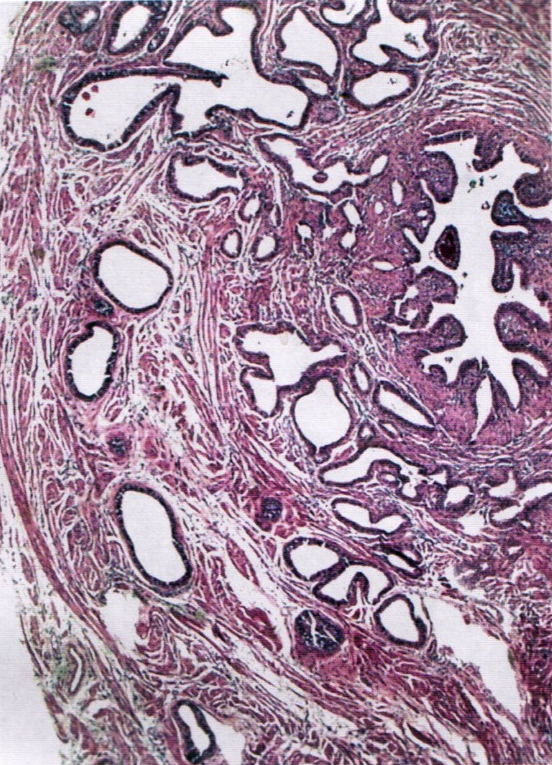

Microscopic (histologic) description

- Regularly spaced glands lined by normal appearing tubal epithelium surrounded by smooth muscle or fibrous tissue

- Tubal lumina are true diverticula that communicate with the central tubal lumen but do not connect with the serosa

- Glands can become cystically dilated (Am J Clin Pathol 1951;21:212)

- No significant atypia, scarring or associated inflammatory / stromal response

- Absence of endometrial stroma differentiates this entity from tubal endometriosis

Microscopic (histologic) images